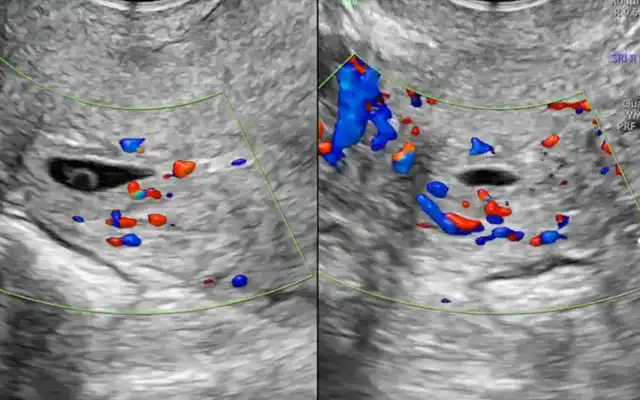

Ultrasound Findings: Transvaginal ultrasound (October 2024) revealed a triangular anechoic niche measuring 6 × 7.8 × 6 mm, located 30 mm above the external os, with a residual myometrial thickness of 5.9 mm (53% of adjacent myometrium). The right ovary was adherent to the uterus; the left ovary contained a simple follicular cyst. Mild adenomyosis was noted in the fundus.